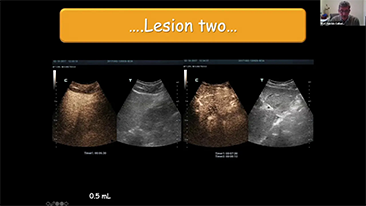

Solusi Pencitraan Umum Resona dari Mindray membantu para dokter mewujudkan diagnosis dan hasil pengobatan yang lebih akurat dan efisien melalui pemerik aplikasi subdivisi yang komprehensif dan alat bantu aplikasi klinis yang efisien.

Lingkungan medis saat ini telah menjadi lebih kompleks, dengan peningkatan jumlah kasus yang sulit dan beban kerja.